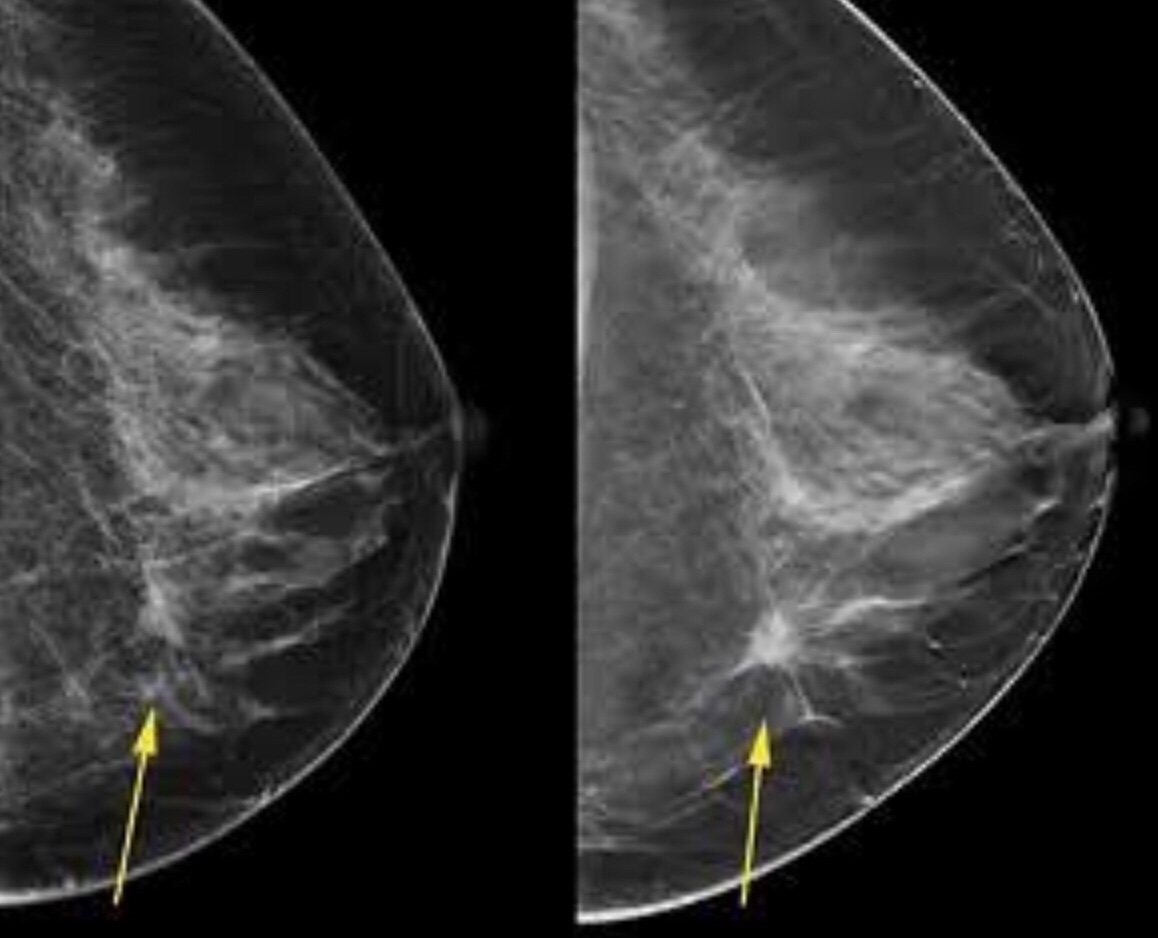

Spiculated lesions with greater density indicate malignancy. Certain patterns of calcification also suggest malignancy.

Clustered irregular microcacifications also suggest malignancy especially when there is distortion of the surrounding breast tissue. V and Y shaped calcifications also suggest malignancy.